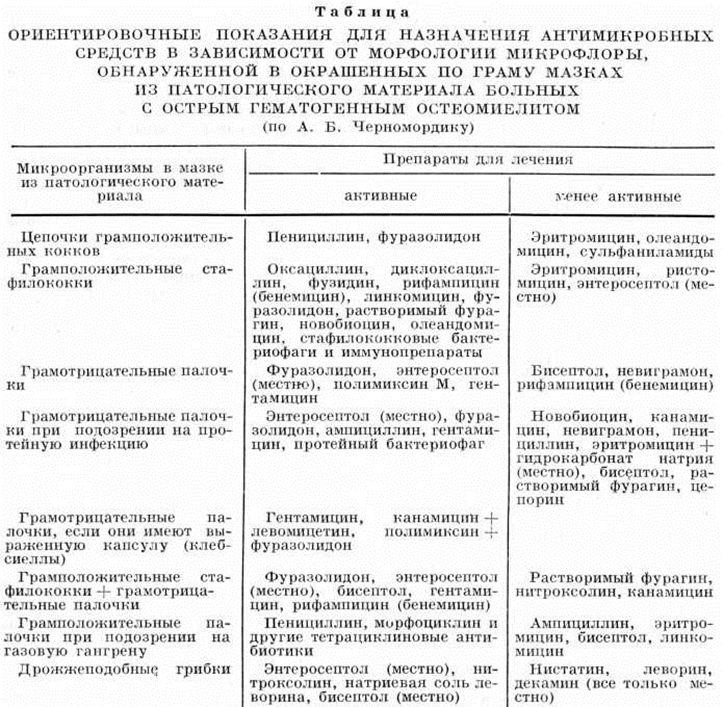

Необходимость соблюдения принципа этиотропности в условиях высокой полирезистентности микробов делает обязательным определение возбудителя и его чувствительности к антибиотикам, что требует определённого времени. С целью быстрейшего начала этиотропной терапии можно использовать ориентировочный метод А. Б. Черномор дика: на предметное стекло наносят и окрашивают по Граму патологический материал; в пределах часа по количеству, форме и отношению бактерий к окраске удаётся правильно подобрать большинству больных антимикробные препараты в соответствии с разработанной для этих целей таблицей (смотри полный свод знаний табл.).

|

|  |

| ||

После проведения полноценного бактериологические исследования в назначенное лечение вносят необходимые изменения. С целью своевременной корректировки антибактериальной терапии через каждые 7 дней производят повторные антибиотикограммы.